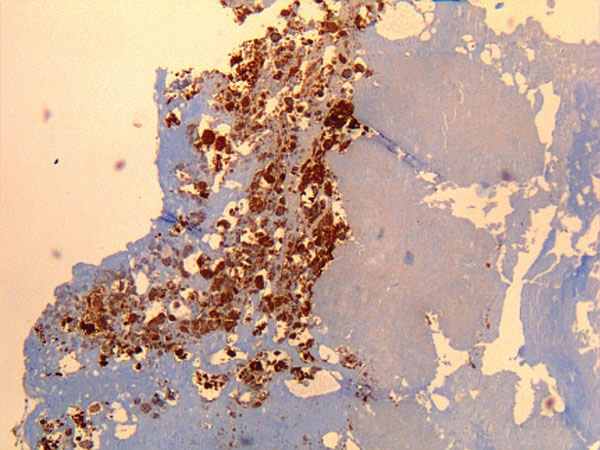

- Inmunofluorescencia indirecta del tejido infectado. Técnica más utilizada para diagnosticar la infección por Coxiella burnetii. Esta prueba sirve básicamente para determinar la presencia de anticuerpos contra la bacteria. El procedimiento es el siguiente: primero, se administra el factor reumatoide, para eliminar las posibilidades de algún falso positivo por detección de Inmunoglobulinas IgM. Seguidamente, sobre un portaobjetos se colocan antígenos de la bacteria. Luego, sobre este sustrato se coloca una muestra del tejido. Si en la muestra está la bacteria, se formarán allí anticuerpos contra ella y, en consecuencia, se forma el conocido complejo “antígeno-anticuerpo”. Inmediatamente, a esto se le agrega una anti inmunoglobulina humana conjugada con fluoroformo. Esta inmunoglobulina reacciona con el anticuerpo del complejo antígeno-anticuerpo que se formó inicialmente. Finalmente, se ve en microscopio de inmunofluorescencia y allí se confirma el diagnóstico.